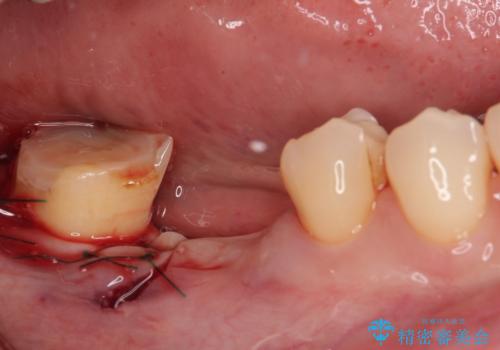

一番奥の歯は歯肉から露出している高さが少なく、クラウンを装着する不十分であったため、歯冠長延長術を行うこととしました。